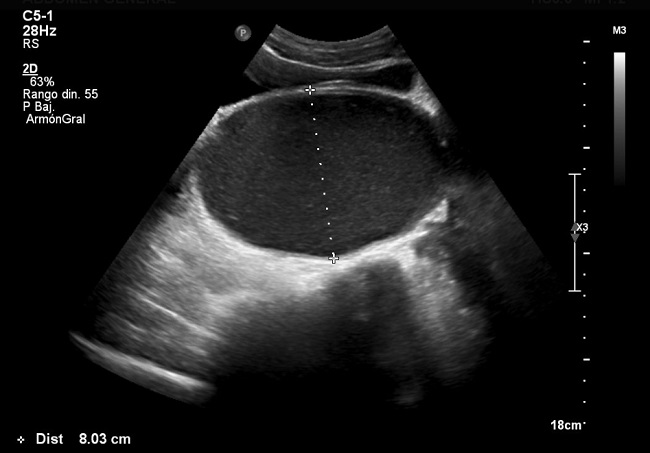

A los diez días acude de nuevo por dolor abdominal intenso que no cede con analgésicos, la despierta por la noche y tiene estreñimiento desde hace un mes. No refiere síntomas miccionales. En la exploración, el estado general es bueno, está afebril, con cardiorrespiratorio normal; se aprecia una gran tumoración abdominal móvil, fluctuante, como si tuviera contenido líquido, de forma alargada, de un tamaño aproximado de 7 × 4 cm, localizada en hipogastrio y fosa iliaca izquierda. Se solicita una ecografía abdominal urgente, en la que se observa una voluminosa lesión quística que ocupa el hipogastrio por detrás de la vejiga, con contenido ligeramente ecogénico, homogéneo, de 16,7 × 8 cm de diámetro, que sugiere como primera posibilidad de diagnóstico hematocolpos por himen imperforado (HIM) (Fig. 1).